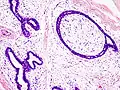

The diagnostic findings on needle biopsy consist of abundant stromal cells, which appear as bare bipolar nuclei, throughout the aspirate; sheets of fairly uniform-size epithelial cells that are typically arranged in either an antler-like pattern or a honeycomb pattern. These epithelial sheets tend to show typical metachromatic blue on Diff-Quik staining. Foam cells and apocrine cells may also be seen, although these are less diagnostic features.[8][9] The gallery images below demonstrate these features.

Fibroadenoma of the breast is a benign tumor composed of a biplastic proliferation of both stromal and epithelial components.[12][13] This biplasia can be arranged in two growth patterns: pericanalicular (stromal proliferation around epithelial structures) and intracanalicular (stromal proliferation compressing the epithelial structures into slit-like spaces).

These tumors characteristically display hypovascular stroma compared to malignant neoplasms.[2][14][9] Furthermore, the epithelial proliferation appears in a single terminal ductal unit and describes duct-like spaces surrounded by a fibroblastic stroma. The basement membrane is intact.[15]